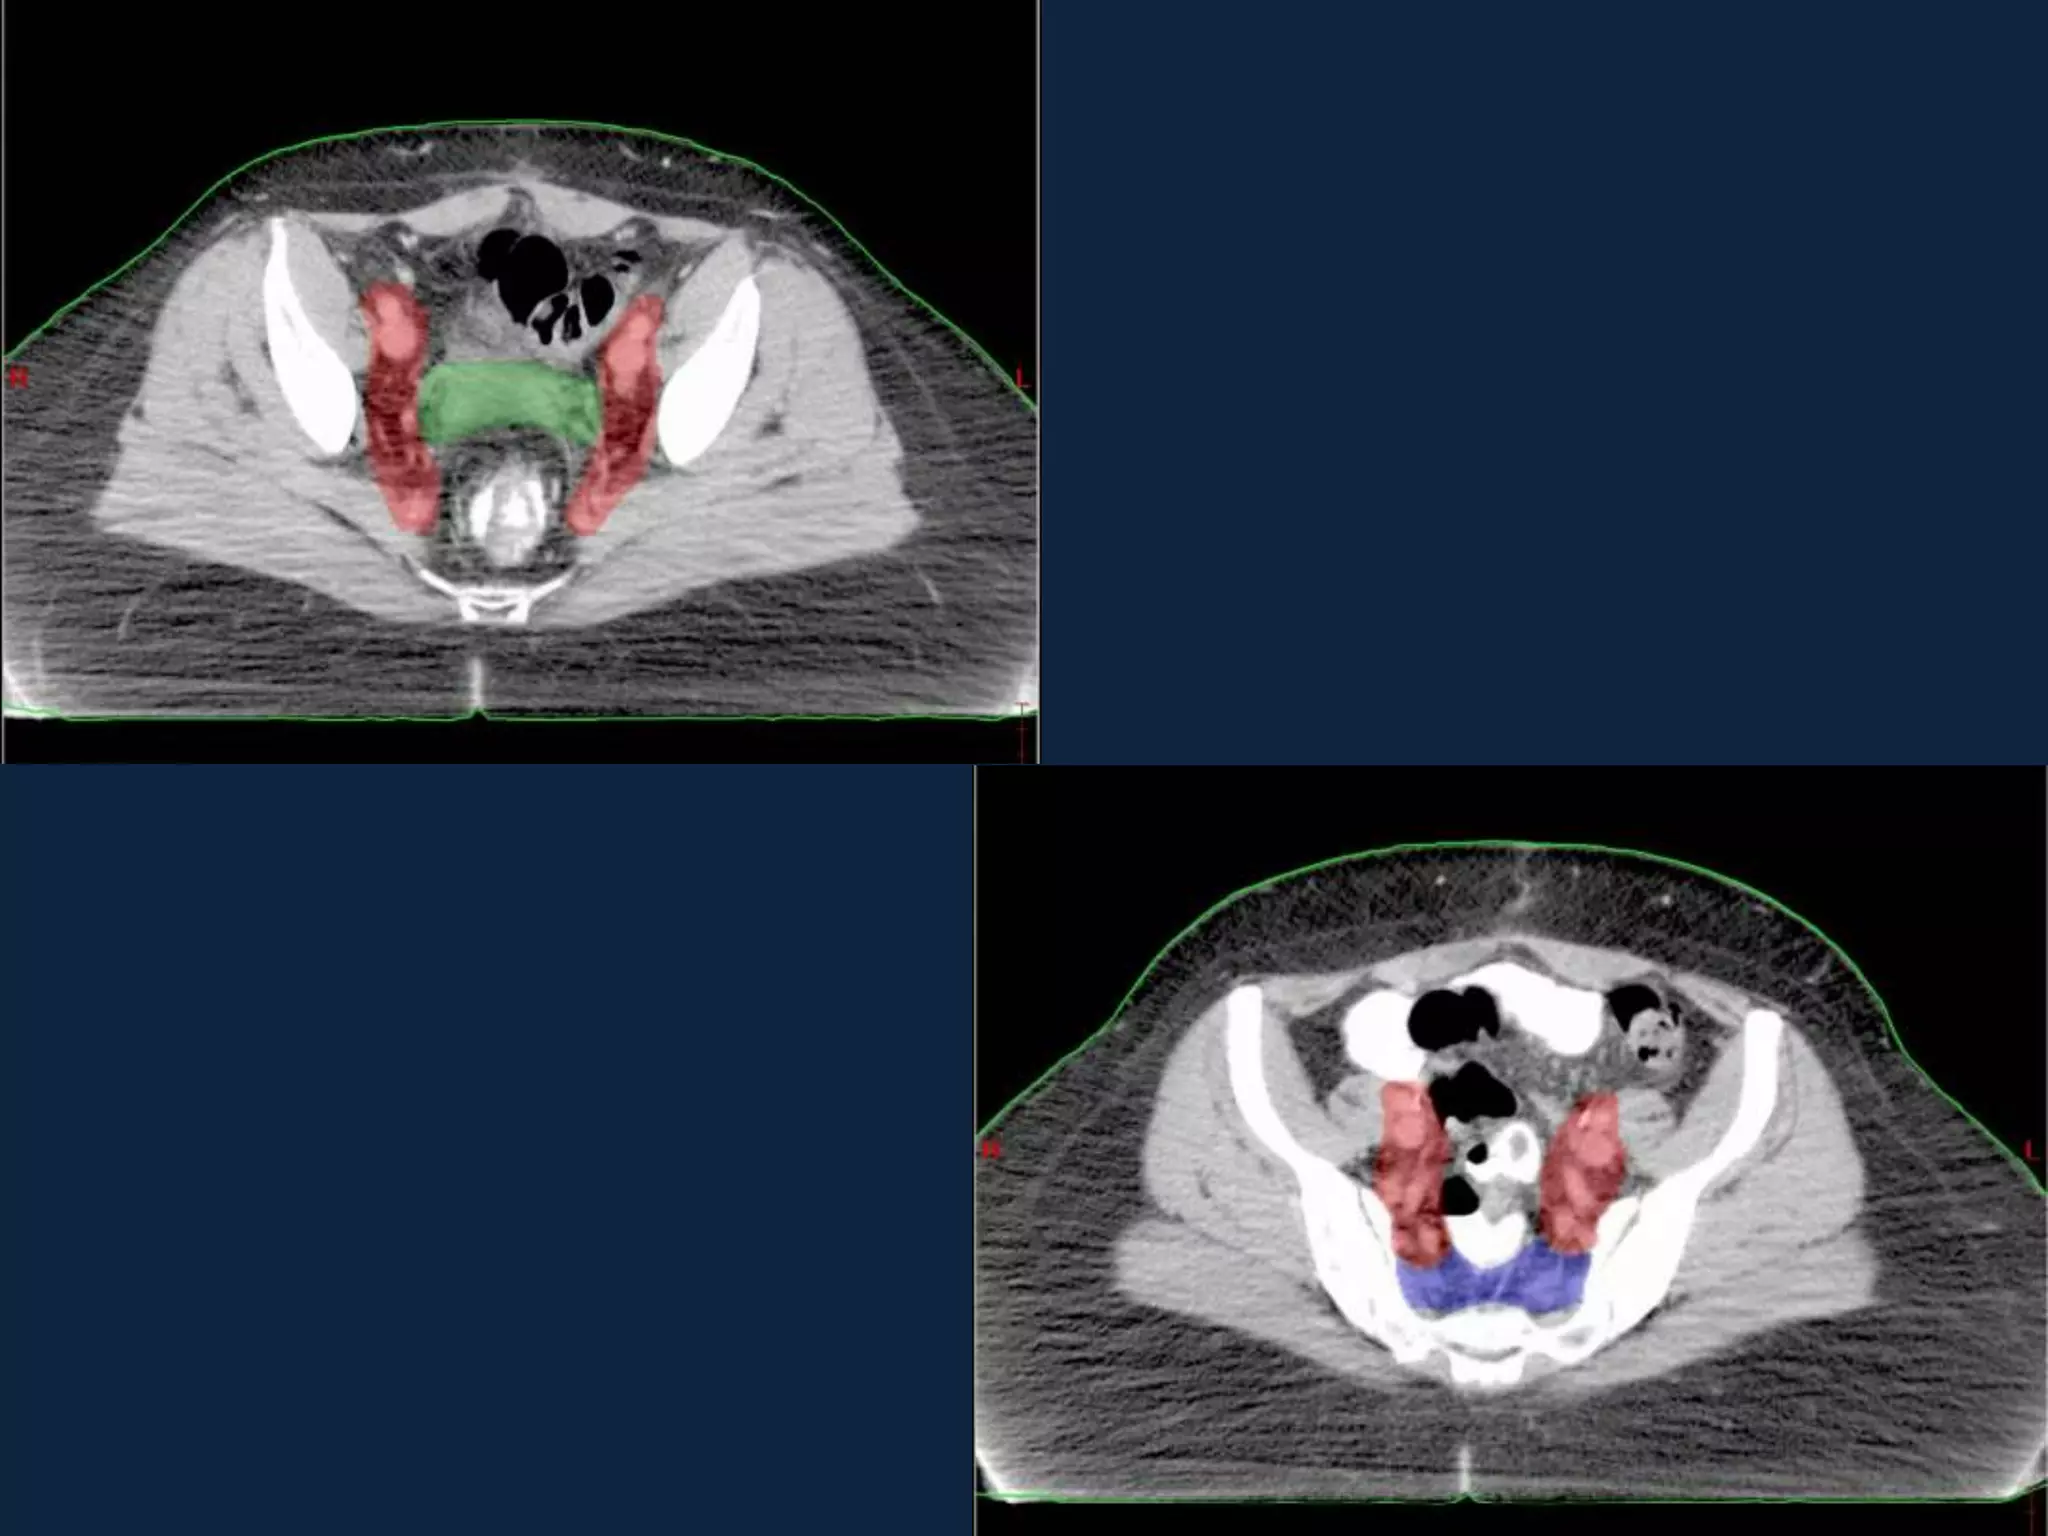

TARGET VOLUME DELINEATION

OAR

IMRT vs CONFORMAL RT

• Pelvic IMRT reduces acute patient reported GI

and GU toxicity compared to standard pelvic RT.

• Pelvic IMRT improves quality of life with regard

to physical functioning and other treatment

effects during treatment .

• Longer term follow up will be needed to

determine if these differences in acute toxicity

result in lower rates of late toxicity.

• Pelvic IMRT reduces need for anti-diarrheal

medications as compared to standard pelvic RT.